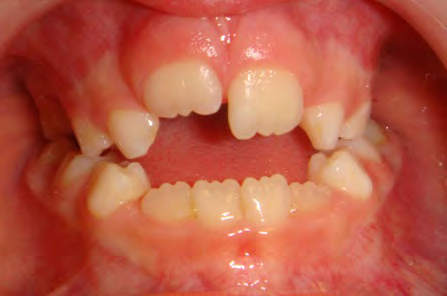

All of the patients below had been told they required extractions by orthodontists, some insisting that they could not be treated without extractions.

They were all treated without extractions, head gear or facemasks at Vakresmil and represent just a small sample of cases treated between 2004–2014.

The patient below had severe crowding of both upper canines and the lower right 5. The upper 4’s and 2’s were actually in contact.

Below are cases treated at Vakresmil without extractions within the last three years. The families had been told, “It is simply not possible for your child to be treated without extractions” by orthodontists. Judge for yourself if that was right or wrong.